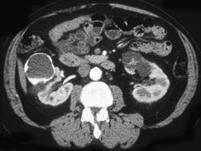

女,34岁,请根据所示图像,选择最可能诊断 ( )A、双肾多发囊肿并钙化B、囊性肾癌C、单纯性肾囊肿D、双肾多发单纯性肾囊肿E、多囊肾

问题 女,34岁,请根据所示图像,选择最可能诊断 ( )

选项 A、双肾多发囊肿并钙化 B、囊性肾癌 C、单纯性肾囊肿 D、双肾多发单纯性肾囊肿 E、多囊肾

答案 A